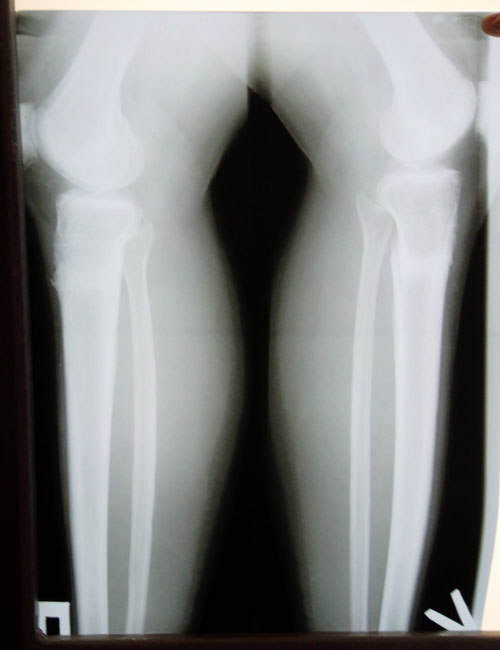

Дата операции 14.11.2013г.

Дата снятия аппаратов 24.03.2014г.

Срок лечения 130 дней.